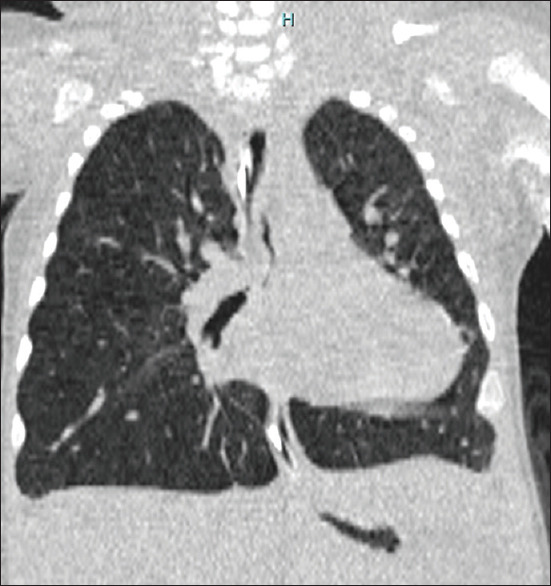

This is a case of a 3-year-old child who presented with long-segment tracheal stenosis (LSTS) and complex congenital cardiovascular disease for surgical intervention. The ideal operation for this child will include slide tracheoplasty and multiple cardiac lesion repairs. However, the low birth weight and extremely young age present a dilemma as to whether to perform total repair simultaneously or in stages. Age and weight by which the first surgical procedure was done, cardiovascular abnormality details, preoperative respiratory support, preoperative tracheobronchomalacia, cardiopulmonary bypass, the complexity of the surgery, and preoperative extracorporeal membrane oxygenation support are known to be predictive factors of long-term outcomes. Comparative studies between simultaneous and staged operations have shown that it is best to manage children with LSTS and complex cardiovascular anomalies in stages.

Abstract Image